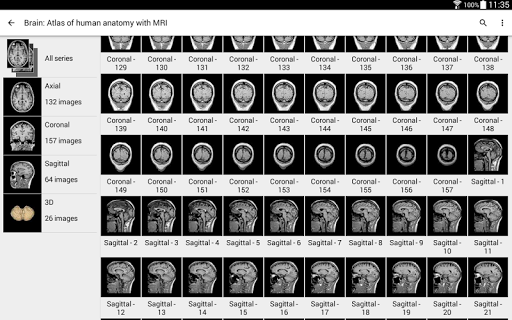

e-Anatomy memiliki lebih dari 26.000 gambar yang berisi serangkaian gambar dalam tampilan aksial, koronal, dan sagital serta radiografi, angiografi, gambar diseksi, bagan anatomi, dan ilustrasi. Semua gambar medis diberi label dengan cermat, lebih dari 967.000 label tersedia dalam 12 bahasa termasuk Terminologia Anatomica Latin.

- Gulir set gambar dengan menyeret jari Anda

- Perbesar dan perkecil